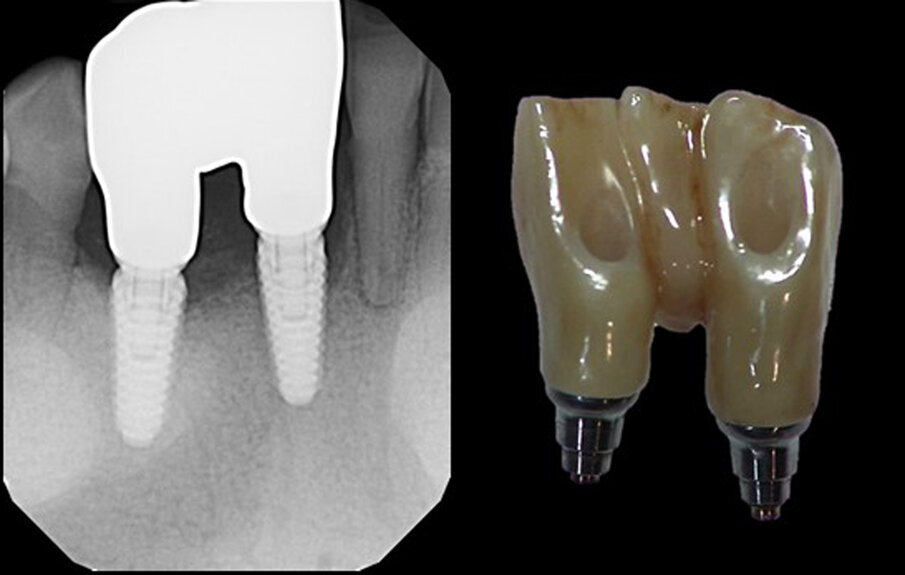

Owing to the pandemic and shutdown, a delay in the return of the patient to initiate the prosthetic stage of treatment resulted. When the patient returned, the implants were exposed with a split-thickness flap. An implant stability quotient value of 80 was recorded for the central incisor implant and of 84 for the canine implant, and healing abutments were placed. A radiograph was taken to check the status of the implants (Fig. 14b). An open-tray impression was captured, opposing impressions taken and a maxillomandibular relationship record taken. Healing abutments were replaced, and the impressions were sent to the laboratory for fabrication of the prosthesis.

Figs. 14a & b: Periapical radiographs of the implant placement (a) and healing abutments placed (b).

Figs. 15a & b: Radiograph of the denitive restoration (a) and the denitive restoration displaying the lingual access openings (b).

Two weeks later, the laboratory work was returned, and the patient presented for insertion. The healing abutments were removed, and the screw-retained three-unit bridge was tried in, and the fixation screws hand-tightened. A periapical radiograph was taken to verify mating of the prosthesis to the implants (Figs. 15a & b). The screws were tightened with a torque wrench to the manufacturer’s recommended torque, and the screw access channels sealed with PTFE tape and flowable composite (Figs. 16a & b). The occlusion was checked, and no adjustment was indicated.